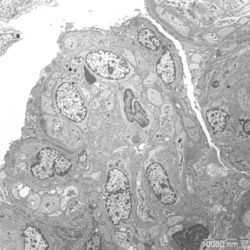

- Figure 3: Electron microscopy image of glomerular lesions in a patient with MPGN